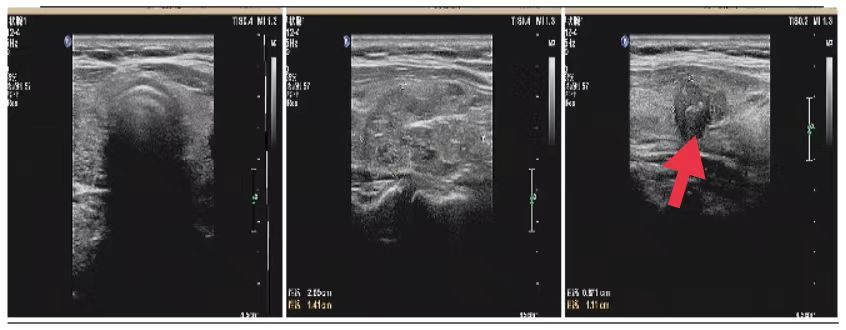

08、**女士,45岁

于2023年8月16日在邯郸仁泰西区体检,乳腺彩超检查提示:右侧乳腺约10点方向见大小约1.4*0.8cm低回声,边界欠清,形态欠规整,诊断:右侧乳腺低回声,建议客户进一步检查,明确病变性质。2023年8月31日跟踪回访,客户已在邯钢医院手术治疗,术后病理诊断乳腺癌。